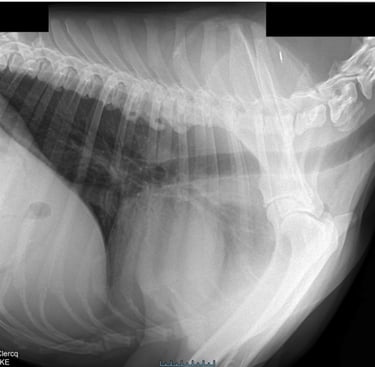

Hartonderzoek - Echocardiografie - Electrocardiografie (EKG) - Radiografie

Radiografie (RX)

Een RX is geschikt om botbreuken, een longontsteking, de hartgrootte, arthrose,....op te sporen.

Als de hond - kat niet lang genoeg stil kan blijven liggen dan is een verdoving noodzakelijk. Voor RX van het heupgewricht is een volledige verdoving noodzakelijk.